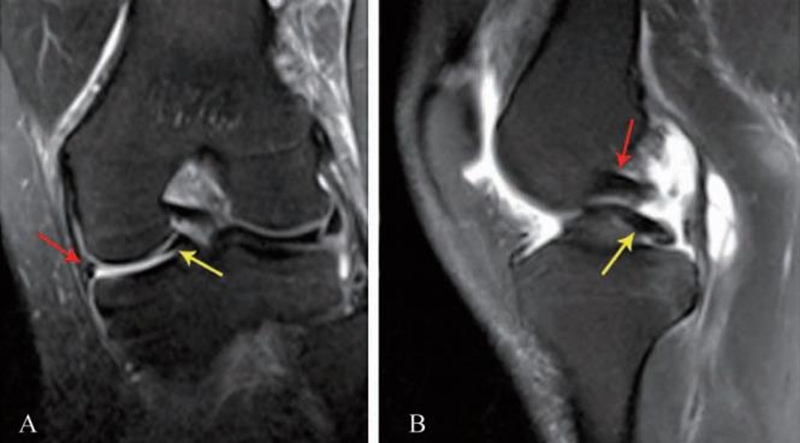

桶柄状撕裂后半月板一分为二,未移位的外侧片为桶,被推移或翻转至髁间窝的内侧部分相当于柄,一般内侧多于外侧,常合并ACL损伤。

MRI上的表现有以下特征:(1)碎块内移征,冠状位或矢状位上髁间窝内可见条状或团块状低信号半月板碎块影。(2)外周残半月板征,冠状位上外围的半月板(母体)明显变小,其内信号可异常或无异常。(3)双PCL征,矢状位上PCL的前下方出现与之平行的低信号条状阴影,实际上是撕裂的内侧半月板向髁间窝内移至PCL的前下方所致。(4)空领结征,矢状位上正常半月板用4~5mm层厚扫描,可见到至少2个层面的半月板呈“领结样”。半月板桶柄状撕裂后,有一部分移位至髁间窝,仅有小部分残留,因此很少能见到完整的“领结”形态。(5)半月板翻转征,矢状位上在半月板前角后方又出现边界清晰的半月板结构,后角变短或消失,也称为双前角征或双峰征。(6)双ACL征,矢状位上ACL的前方或后方出现低信号条状阴影(图5)。

图5 半月板桶柄状撕裂的MRI影像

A. 冠状位内侧半月板母体变小(红色箭头),髁间窝出现异常的半月板节段(黄色箭头);B. 矢状位出现双PCL征,上方为PCL信号(红色箭头),下方为半月板信号(黄色箭头)